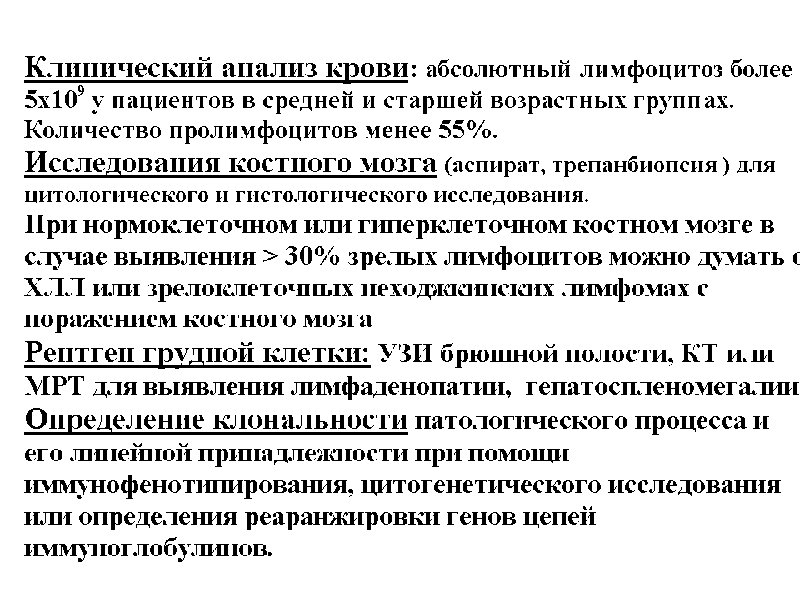

Лимфопролиферативные заболевания 5 курс профессор Моисеев С. И.